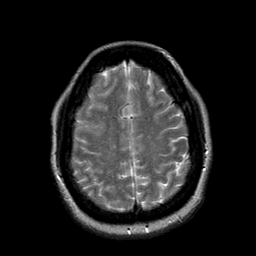

Cerebral hemorrhage, MR Study mr-t2 -- Slice #18

[Home][Help][Clinical] Slice 18